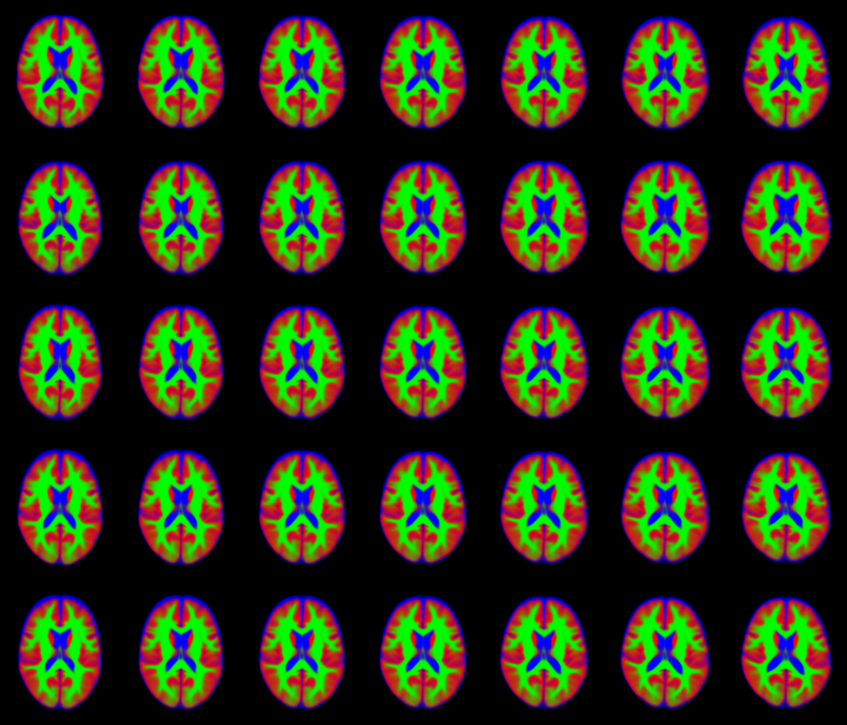

IXI dataset

This example demostrates the multinomial noise model on a single slice through segmented scans from the IXI dataset. The original scans were segmented into grey matter (shown in red), white matter (green) and CSF (blue). The data were fit using 40 components encoding both shape and appearance. These 40 parameters can be used for data mining.

- Original Images (randomly selected from the dataset).

- Full Fit (both shape and appearance).

- Appearance model only.

- Shape model only.

- First 10 modes of variability.